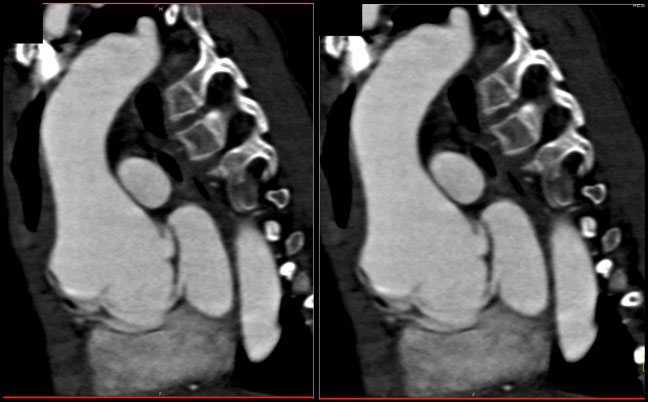

Dilated Aortic Root